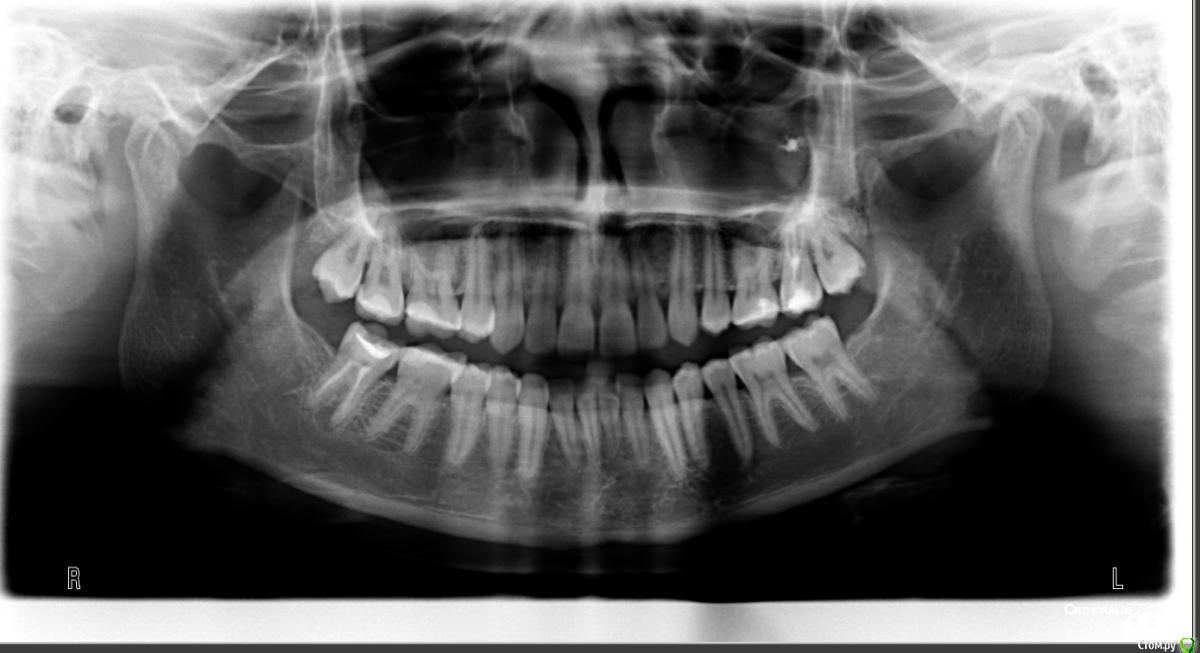

katiakatia Опубликовано 25 августа, 2015 Поделиться Опубликовано 25 августа, 2015 Добрый день, уважаемые стоматологи!Посмотрите, пожалуйста, рентген снимок. Нижний ряд, справа, последний зуб. Что это может быть? Инфекция? Мне объясняли на иностранном, я мало что поняла..Поставили пломбу на этот зуб ровно год назад, на данный момент меня ничего не беспокоит, ничего не болит.И вообще в целом, остальные зубы в порядке судя по снимку? Большое спасибо за ответы Ссылка на комментарий

diesel87 Опубликовано 25 августа, 2015 Поделиться Опубликовано 25 августа, 2015 Снимок свежий? Перелечивать каналы нужно в этом зубе, если прошел год после лечения. 3 Ссылка на комментарий